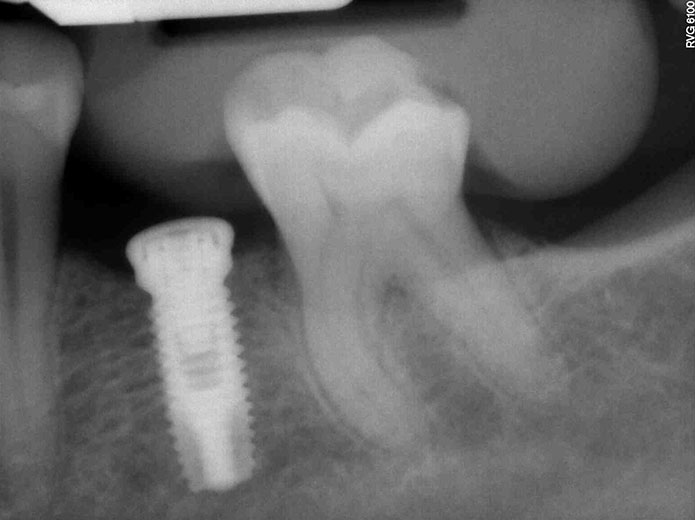

Αποκατάσταση έλλειψης μεμονωμένου δοντιού

Όταν λείπει ένα δόντι, τοποθετείται ένα μεμονωμένο εμφύτευμα στην περιοχή, το οποίο υποκαθιστά το δόντι τόσο λειτουργικά, όσο και αισθητικά.